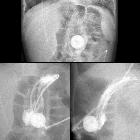

Toddler with

problems feeding through the jejunostomy port of their gastrojejunostomy tube. AXR (above) shows the tip of the jejunostomy tube projects over the body of the stomach. AP (below left) and lateral (below right) images obtained after injecting water soluble contrast through the jejunostomy port of the gastrojejunostomy tube shows contrast outlining the rugae of the stomach. There is no contrast in the duodenum or jejunum.The diagnosis was gastrojejunostomy tube malfunction with the tip of the jejunostomy tube having been pulled back into the stomach.